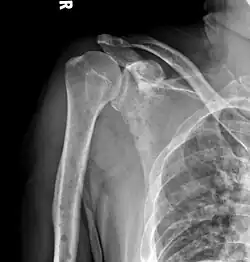

The diagnostic examination of a person with suspected multiple myeloma typically includes a skeletal survey. This is a series of X-rays of the skull, axial skeleton, and proximal long bones. Myeloma activity sometimes appears as "lytic lesions" (with local disappearance of normal bone due to resorption) or as "punched-out lesions" on the skull X-ray ("raindrop skull"). Lesions may also be sclerotic, which is seen as radiodense.[76] Overall, the radiodensity of myeloma is between −30 and 120 Hounsfield units (HU).[77] Magnetic resonance imaging is more sensitive than simple X-rays in the detection of lytic lesions. An MRI may supersede a skeletal survey, especially when vertebral disease is suspected. Occasionally, a CT scan is performed to measure the size of soft-tissue plasmacytomas. Nuclear Medicine Bone scans are typically not of any additional value in the workup of people with myeloma (no new bone formation; lytic lesions not well visualized on nuclear bone scan).

Humerus with multiple myeloma lesions -